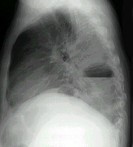

- 单项选择题男,36岁, 胸痛半月伴发高热,胸片发现占位性病变, CT检查如图,最可能的诊断为 ( )

A、左下肺肺脓肿

B、左下肺癌并空洞形成

C、左侧胸腔积脓

D、左下肺囊肿

E、左下肺肺炎